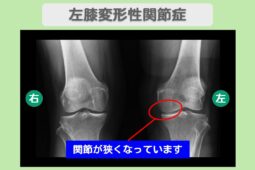

【痛み劇的改善で手術回避】 腰椎椎間板ヘルニア・両膝変形性関節症 70代女性

“リペア幹細胞” 痛み10段階中10が3に!高齢でも諦めなくてよかった!左変形性膝関節症 80代 女性